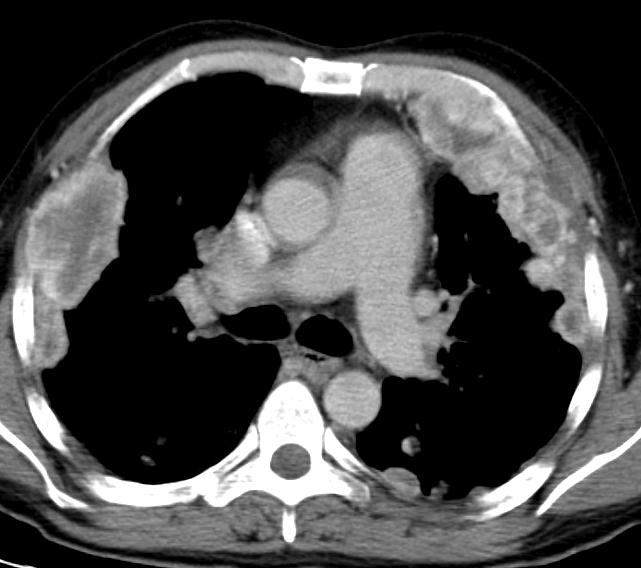

Renal cell to pleura